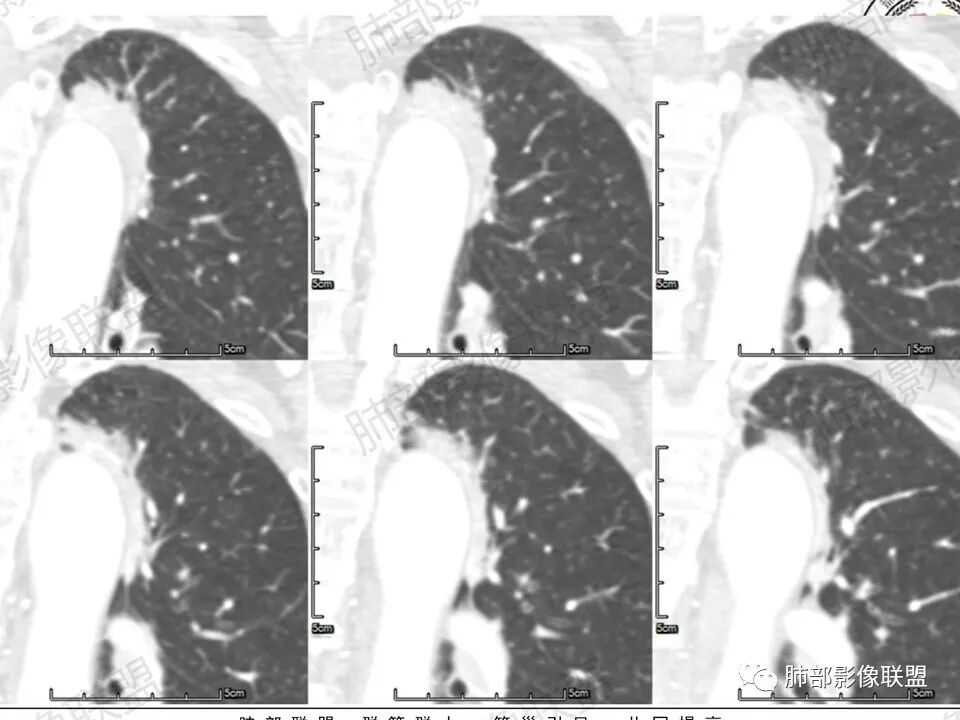

老年女性,体检发现左上肺主动脉弓旁占位,脂肪间隙清晰,边缘部分光滑、部分毛糙,似有毛刺、分叶,似有边界清楚的GGO,内部大部密度均匀,有条索状低密度(支气管粘液栓?),增强检查见均匀明显强化,延迟强化明显(CT值增加近80Hu)。边缘见支气管提示肺内病变。整体考虑炎性可能,炎性病变的强化似乎是以动脉期明显,本例延迟强化明显,延迟强化明显的病例可能有:PSP、类癌、淋巴上皮瘤样癌、炎性病变?…………似有分叶及病灶边缘GGO,注意鉴别腺癌。

马春平(张家港市一院胸外科):沿着支气管、肺动脉或主动脉、心缘、膈肌旁生长的腺癌形态会千奇百怪,抓住最重要的一条:找周边沿腺泡囊生长、边界较清的磨玻璃灶。

Coke with ice:病例收缩力偏弱,有磨玻璃,有牵拉支气管扩张,明显强化。可疑栽桩。符合实体型腺癌的表现。需要考虑到粘液腺的可能性。